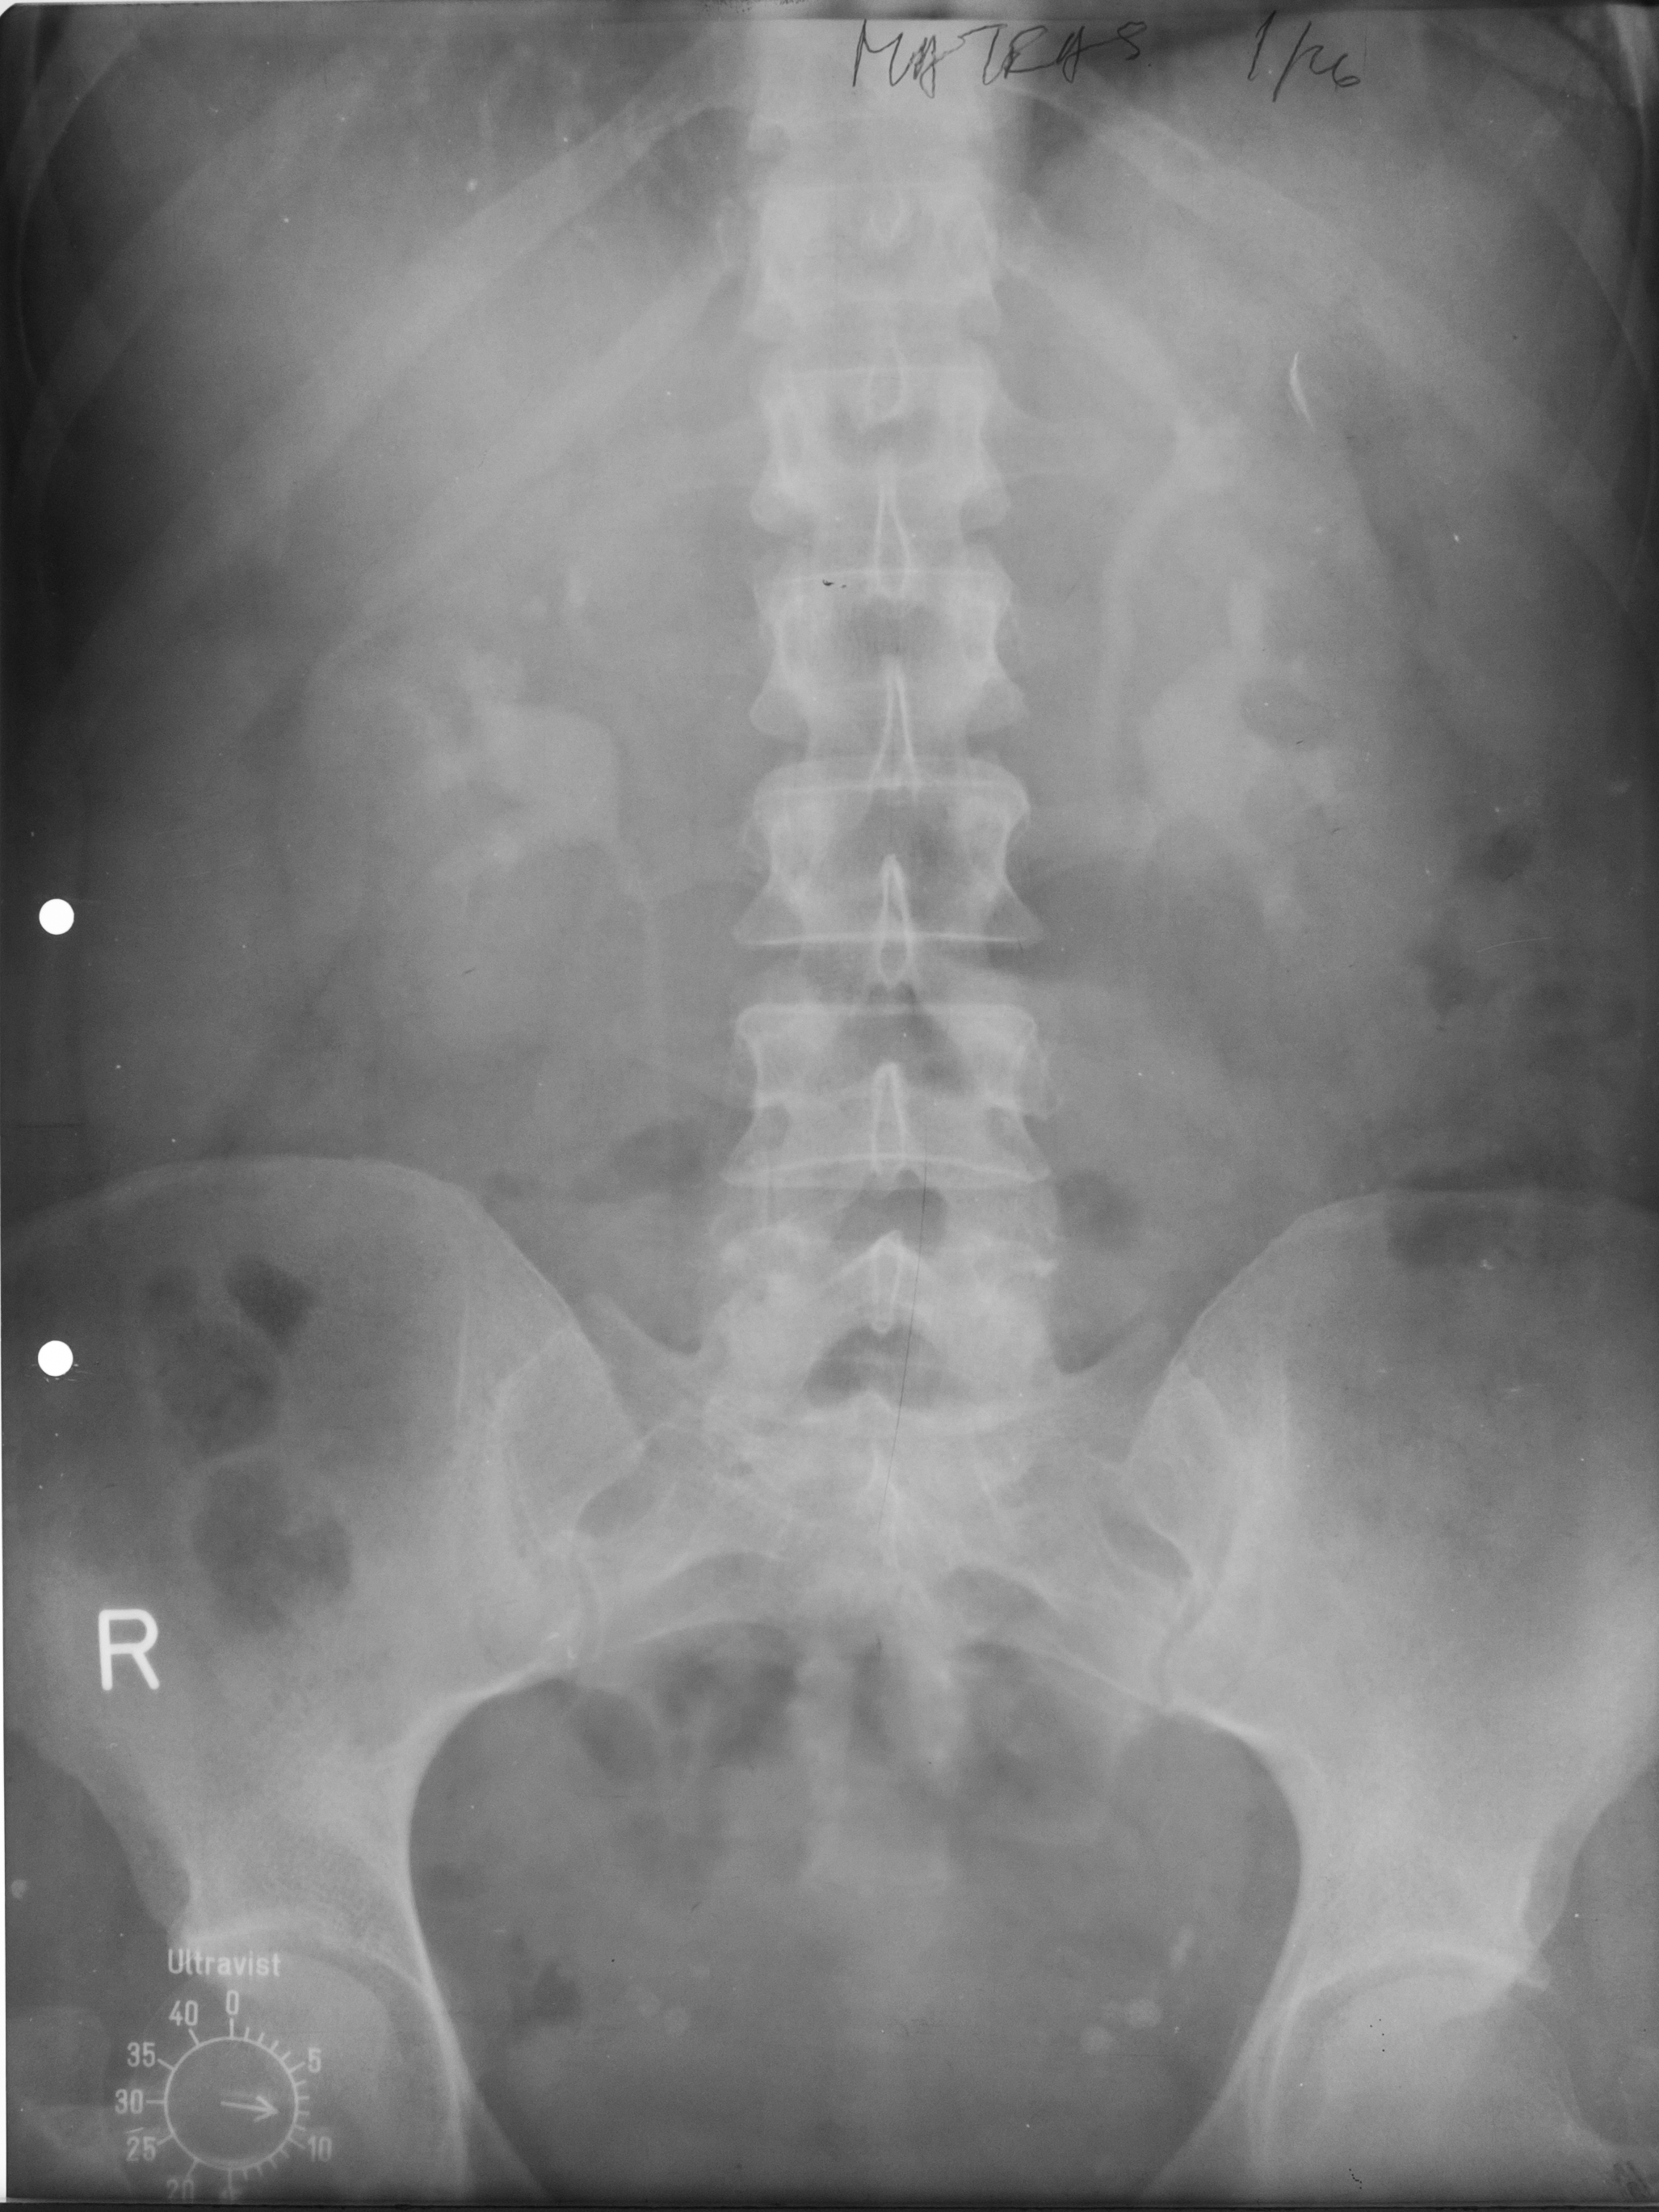

:IMAGINE NORMALA

Urografie cu substanta de contract intravenous, efectuata la 9 minute postinjectare, in care se observa ariile renale, de dimensiuni normale, nefrograma si opacifierea aparatului pielocalicial care este de dimensiuni normale, uretere la nivelul vezicii urinare